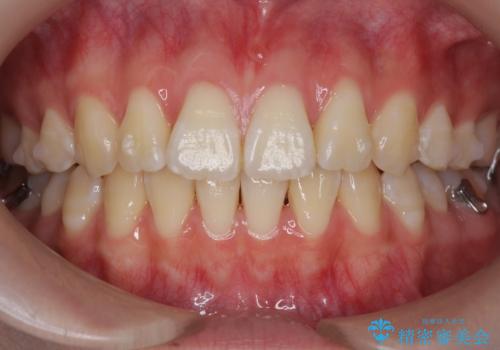

出っ歯 軽度のがたつき インビザラインで

- 20代女性

- インビザライン

- 3年1ヶ月

前歯のずれも治り、しっかり下がりました。

前歯を下げるのに、顎間ゴムを使用していただいています。